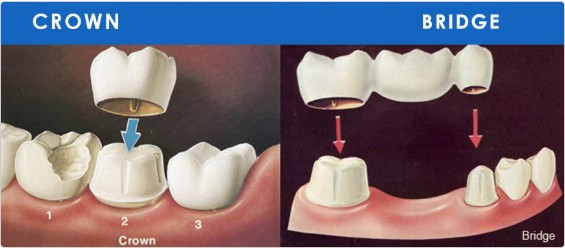

- When a tooth is fractured, has a large,old filling, or is severely damaged by decay, your dentist may recommend the placement of a

crown, or cap

CROWNS

Crowns strenthen and protect the remaining tooth structure and can improve the appreance of your smile.

Types of crowns include the full procelain crowns, the procelain-fused-to-metal crown and the all-metal crown

Fitting a crown requires at least two visits to the dentists office initially the dentist:

- Removes decay and shapes the tooth.

- Makes an Impression.

- Makes and fits a temporary or transitional crown of plastic or metal.

- Patients can resume normal eating and brushing immediately.

- In a subsequent visit the dentist: removes the temporary, fits and adjusts the final crown, cements the crown into place.

BRIDGES

Few incidents have greater impact on dental health and personal appreance than tooth loss. When one or more

teeth are missing the remaining can drift out of position, which can lead to change in the bite the loss of additional teeth,

decay and gum disease.

When tooth loss occurs, your dentist may recommend the placemnt of a bridge. A bridge is one or more

crowns on each side.

- Initially, the dentist prepares teeth on each side of the space to recieve crowns and makes an impression of the entire area.

- Fits a temporary or transitional bridge.

- In a subsequent visit the dentist places, adjusts and cements the fixed bridge.